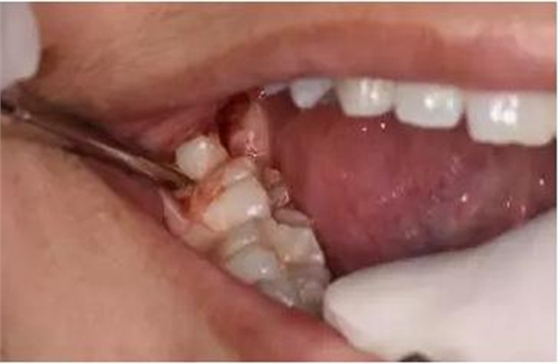

圖6. 從37頰側(cè)中份齦溝內(nèi)開始切開,向磨牙后區(qū)延伸

圖7.切開47遠(yuǎn)中齦溝并延長(zhǎng)至磨牙后區(qū)約1cm。

圖8.形成一個(gè)只有水平切口的小袋形口